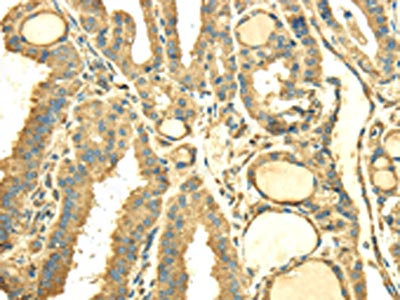

The image on the left is immunohistochemistry of paraffin-embedded Human thyroid cancer tissue using CSB-PA279846(SDF4 Antibody) at dilution 1/40, on the right is treated with fusion protein. (Original magnification: ×200)